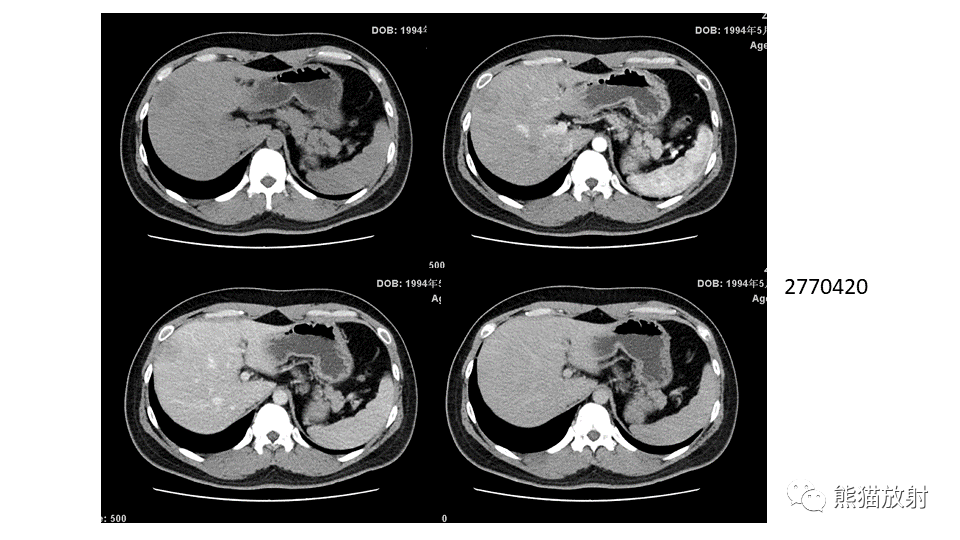

【PPT】肝内胆管细胞癌 VS 肝脓肿